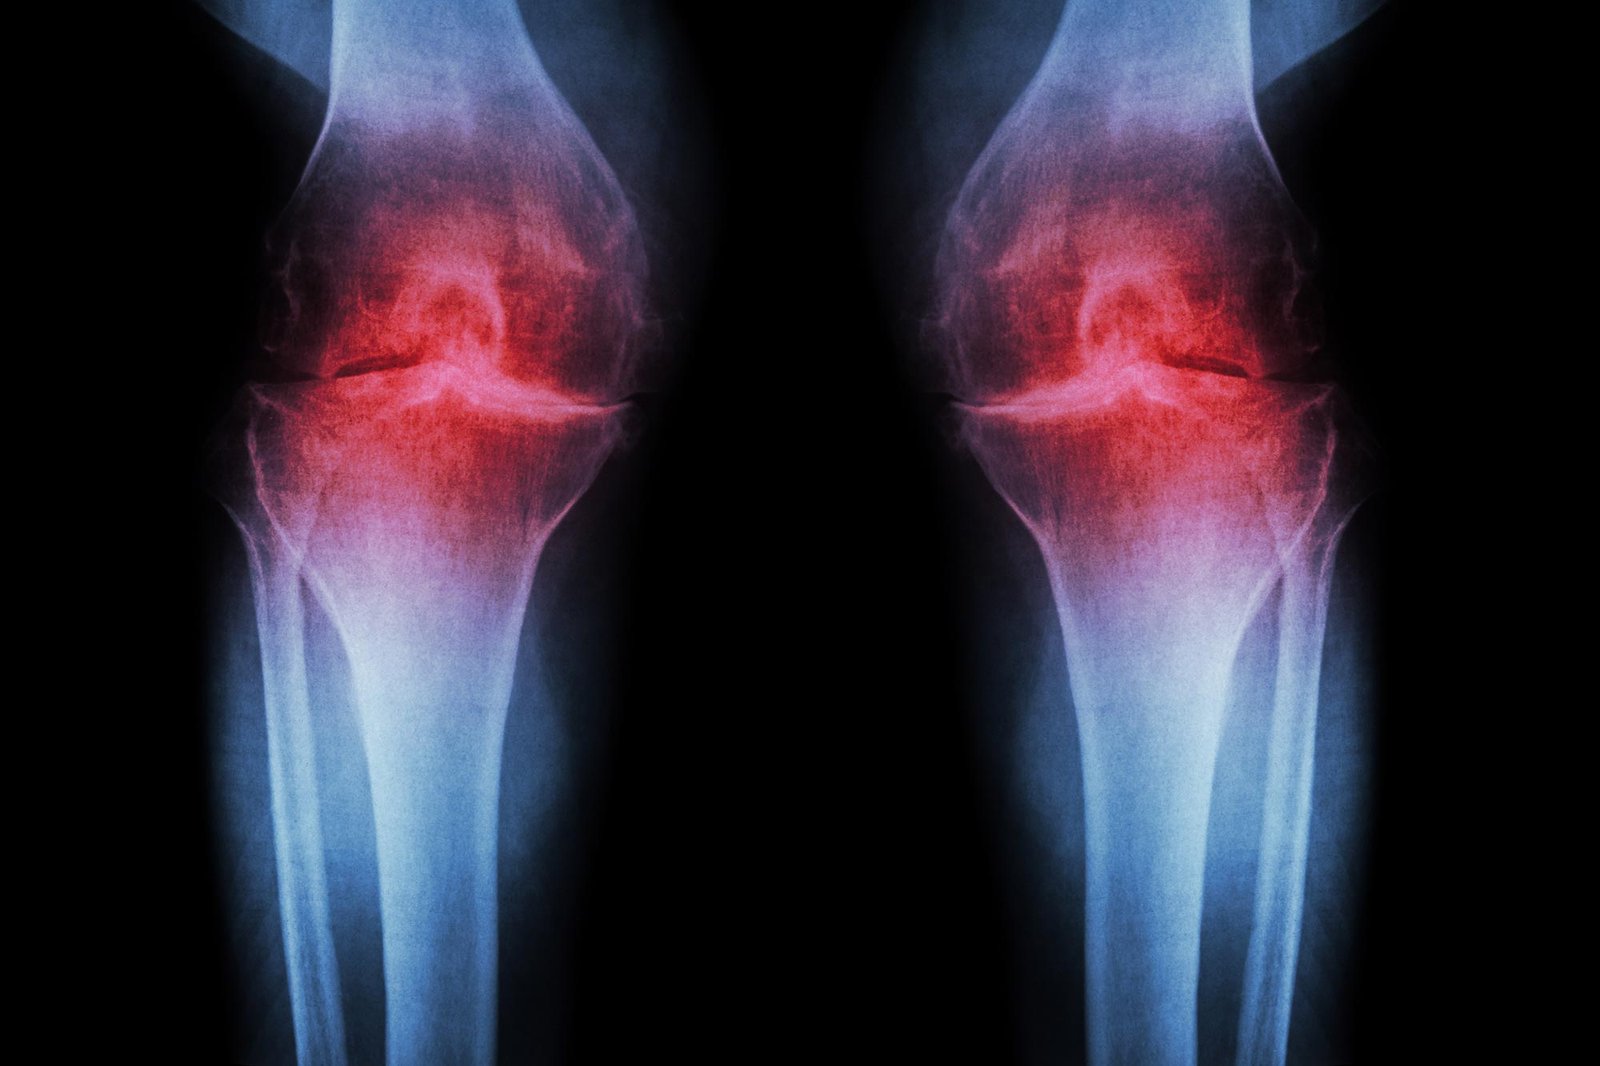

الباحثون في طب ستانفورد أفاد باحثون أن حجب البروتين المرتبط بالشيخوخة يمكن أن يعيد الغضروف الذي يتآكل بشكل طبيعي في ركبتي الفئران الأكبر سنًا. وفي الدراسة، لم يقتصر العلاج عن طريق الحقن على إعادة بناء الغضروف فحسب، بل أوقف أيضًا تطور التهاب المفاصل بعد إصابات الركبة المشابهة لتمزق الرباط الصليبي الأمامي، وهو أمر شائع بين الرياضيين والبالغين النشطين. ويجري بالفعل اختبار نسخة من العلاج نفسه تعتمد على حبوب منع الحمل في تجارب سريرية تهدف إلى علاج ضعف العضلات المرتبط بالشيخوخة.

هناك ثلاثة أنواع رئيسية من الغضروف في جسم الإنسان. الأول، الغضروف المرن، وهو ناعم ومرن ويشكل هياكل مثل الأذن الخارجية. أما النوع الثاني، وهو الغضروف الليفي، فهو كثيف وقوي، ويمتص الصدمات في مناطق مثل ما بين فقرات العمود الفقري. أما الثالث، وهو الغضروف الزجاجي، فهو أملس ولامع، ويوفر سطحًا منخفض الاحتكاك للتشحيم والمرونة في المفاصل مثل الكاحلين والوركين والكتفين وأجزاء من الركبة. الغضروف الهياليني — المعروف أيضًا باسم الغضروف المفصلي — هو الغضروف الأكثر تأثرًا بالتهاب المفاصل العظمي.

يحدث التهاب المفاصل العظمي عندما يتعرض المفصل للضغط بسبب الشيخوخة أو الإصابة أو السمنة. تبدأ الخلايا الغضروفية في إطلاق جزيئات مؤيدة للالتهابات وتكسير الكولاجين، وهو البروتين الهيكلي الأساسي للغضروف. عندما يتم فقدان الكولاجين، يرق الغضروف ويلين؛ ويسبب الالتهاب المصاحب تورم المفاصل والألم، وهي من السمات المميزة للمرض. في الظروف العادية، نادرا ما يتجدد الغضروف المفصلي. على الرغم من أنه تم التعرف على بعض مجموعات الخلايا الجذعية أو الخلايا السلفية القادرة على توليد الغضاريف في العظام، إلا أن محاولات تحديد مجموعات مماثلة من الخلايا في الغضروف المفصلي لم تنجح.